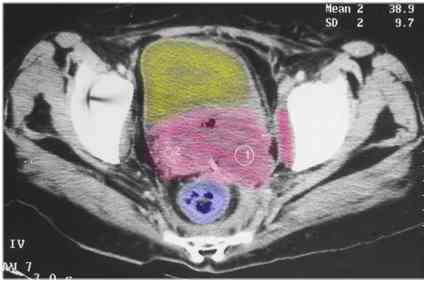

CT Scan Showing  Advanced Cervix Cancer

CT Scan of the pelvis showing a large uterus/cervix mass pushing into the side wall (parametrium)

red = cancer (uterus and cervix) yellow = bladder

blue = rectum